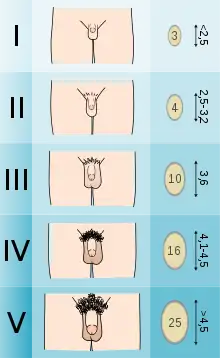

The beads are compared with the testicles of the patient, and the volume is read off the bead which matches most closely in size. Prepubertal sizes are 1–3 ml, pubertal sizes are considered 4 ml and up and adult sizes are 15-25 ml.[3]

The orchidometer can be used to accurately determine size of testes. Discrepancy of testicular size with other parameters of maturation can be an important clue to various diseases. Small testes can indicate either primary or secondary hypogonadism. Testicular size can help distinguish between different types of precocious puberty. Since testicular growth is typically the first physical sign of true puberty, one of the most common uses is as confirmation that puberty is beginning in a boy with delayed puberty. Large testes (macroorchidism) can be a clue to one of the most common causes of inherited generalised learning disability, fragile X syndrome.

Numerous clinical scales and measurement systems exist to define genitals as normal male or female, or "abnormal", including the Prader scale, Quigley scale. and the satirical Phall-O-Meter.